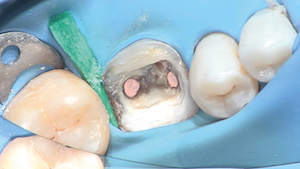

3 - Après reprise endodontique, dépose de l’ensemble du CVI périphérique. Son aspect est discernable après séchage. Un coin de bois protège la digue.